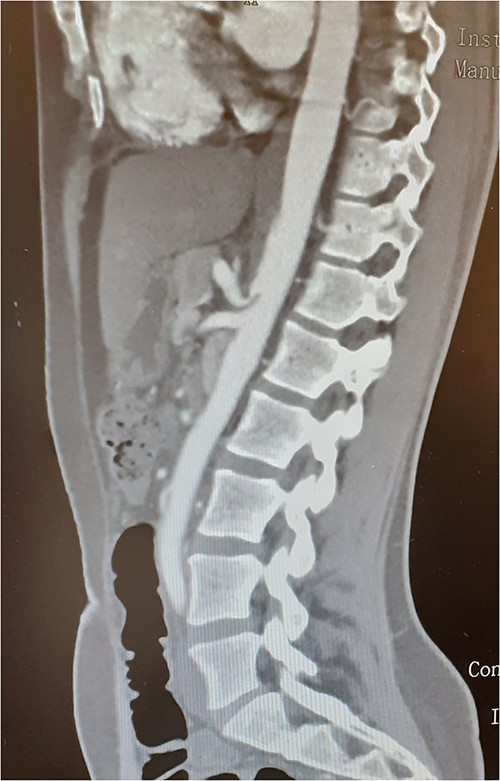

A 37-year-old woman with autoimmune thyroiditis, epilepsy, anti-erythrocyte S antibody and with suspected mixed cryoglobulinemia under study was evaluated for recurrent postprandial abdominal pain with 6 months of evolution, fullness and vomiting with copious meals and weight loss of about 7 kg in 6 months, having already performed a computed tomography angiography (CTA) that revealed MALS (Fig.1). In collaboration with the General Surgery Department, a section of the MAL and lysis of the adhesions by laparoscopic approach was performed. On the third postoperative day, the patient developed a chylous fistula that resolved with conservative strategy including oral diet discontinuation, parenteral nutrition and octreotide. At 1 year follow-up, the patient showed clinical improvement in abdominal pain and food tolerance, and imagiological improvement (Fig.2).